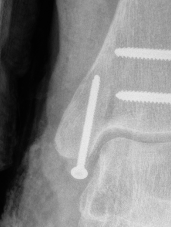

Fixation options

| Screw fixation | Tension band wire | Buttress plate |

|---|---|---|

| Type C: transverse fractures |

Type B: too small for two screws |

Type D: Vertical fractures |

Screw fixation

AO surgery reference medial malleolus lag screws